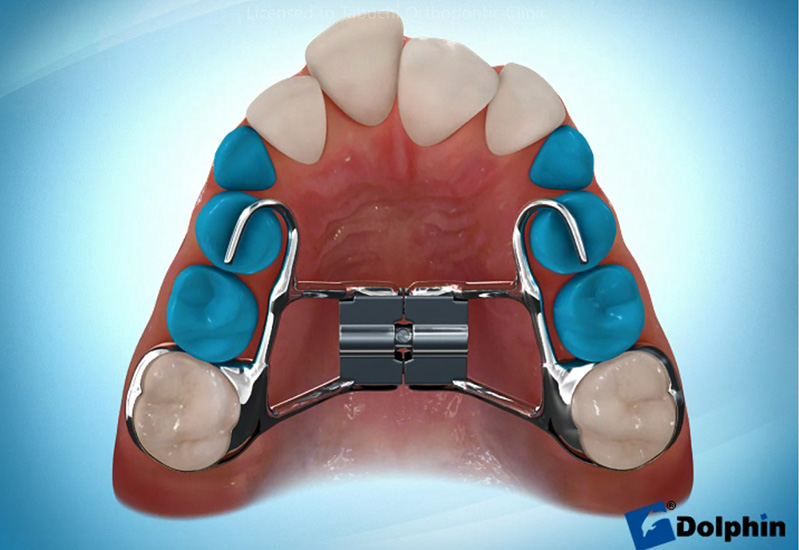

急速拡大装置

上顎の骨の幅を大きく拡げる装置です。子どもの成長期には、上顎の骨が完全にくっついていないことを利用して広げます。混合歯列期に行うことで、永久歯の生えてくるスペースを確保し、抜歯を回避することにも繋がります。